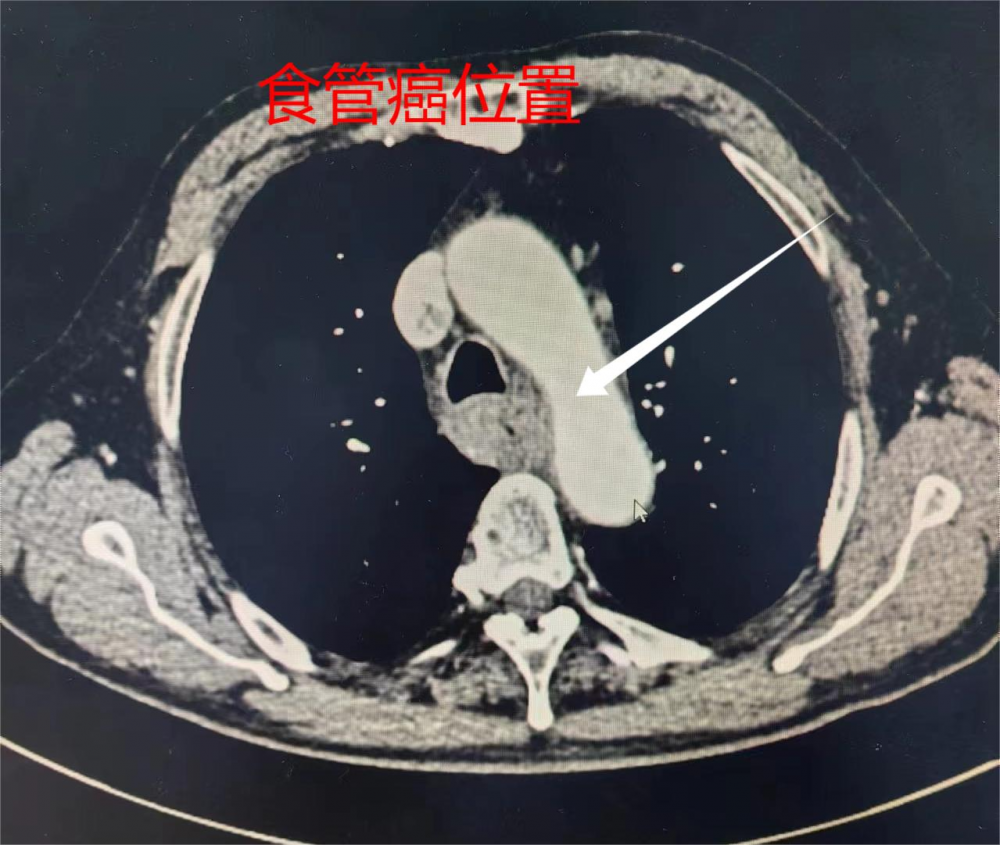

王某某,72歲,近一個月來吞咽困難,有梗噎感等癥狀。經(jīng)病理活檢確診為食管癌。入院后,胸外科主任季運來發(fā)現(xiàn)該患者胃鏡提示:病灶距咽喉部僅8cm,位置較高;胸部強化CT亦提示食管癌外侵較重,與氣管關(guān)系緊密。針對此病例,傳統(tǒng)的手術(shù)方式為左側(cè)開胸手術(shù),但是存在不能完整切除病變、甚至損傷氣管的較大風(fēng)險。為實現(xiàn)根治,并將手術(shù)并發(fā)癥風(fēng)險降到最低,經(jīng)再三論證,胸外科醫(yī)療團(tuán)隊最終決定行頸胸腹三切口食管癌根治手術(shù)。手術(shù)經(jīng)右側(cè)開胸切除食管病變,腹部正中切口游離胃并縮成管狀胃,在左側(cè)頸部行食管與管狀胃的吻合。相較于傳統(tǒng)手術(shù),該術(shù)式過程復(fù)雜,對術(shù)者技術(shù)、術(shù)中麻醉和手術(shù)護(hù)理要求更高,但能更好地保證手術(shù)質(zhì)量,降低了術(shù)后并發(fā)癥的幾率。手術(shù)歷經(jīng)5個多小時。術(shù)后第2天就通過十二指腸營養(yǎng)管注入流質(zhì)食物進(jìn)行腸內(nèi)營養(yǎng),第3天即下床活動,第7天正常經(jīng)口進(jìn)食流質(zhì)飲食,未出現(xiàn)任何并發(fā)癥。